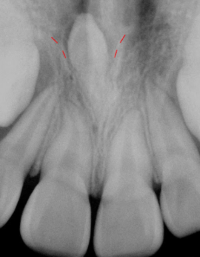

과잉치는 다양한 형태로 나타날 수 있으며, 가장 일반적인 형태는 앞니 사이에 생기는 "정중과잉치(mesiodens)"입니다. 이러한 과잉치는 치열의 배열을 방해하거나 치아 맹출 경로를 막을 수 있습니다.

과잉치의 존재는 주변 치아의 정상적인 발육을 방해할 수 있으며, 경우에 따라서는 통증을 유발하거나 치아 배열의 이상을 초래할 수 있습니다. 진단은 주로 치과 엑스레이를 통해 이루어지며, 치료는 과잉치의 위치와 환자의 상태에 따라 다릅니다. 일반적으로는 외과적 발치가 필요할 수 있으며, 이후에는 교정 치료를 통해 정상적인 치열을 유지합니다.

-역위: 다른 치아와 반대방향으로 거꾸로 올라가는 방향으로 나는 과잉치를 의미합니다. (맨 위 사진)